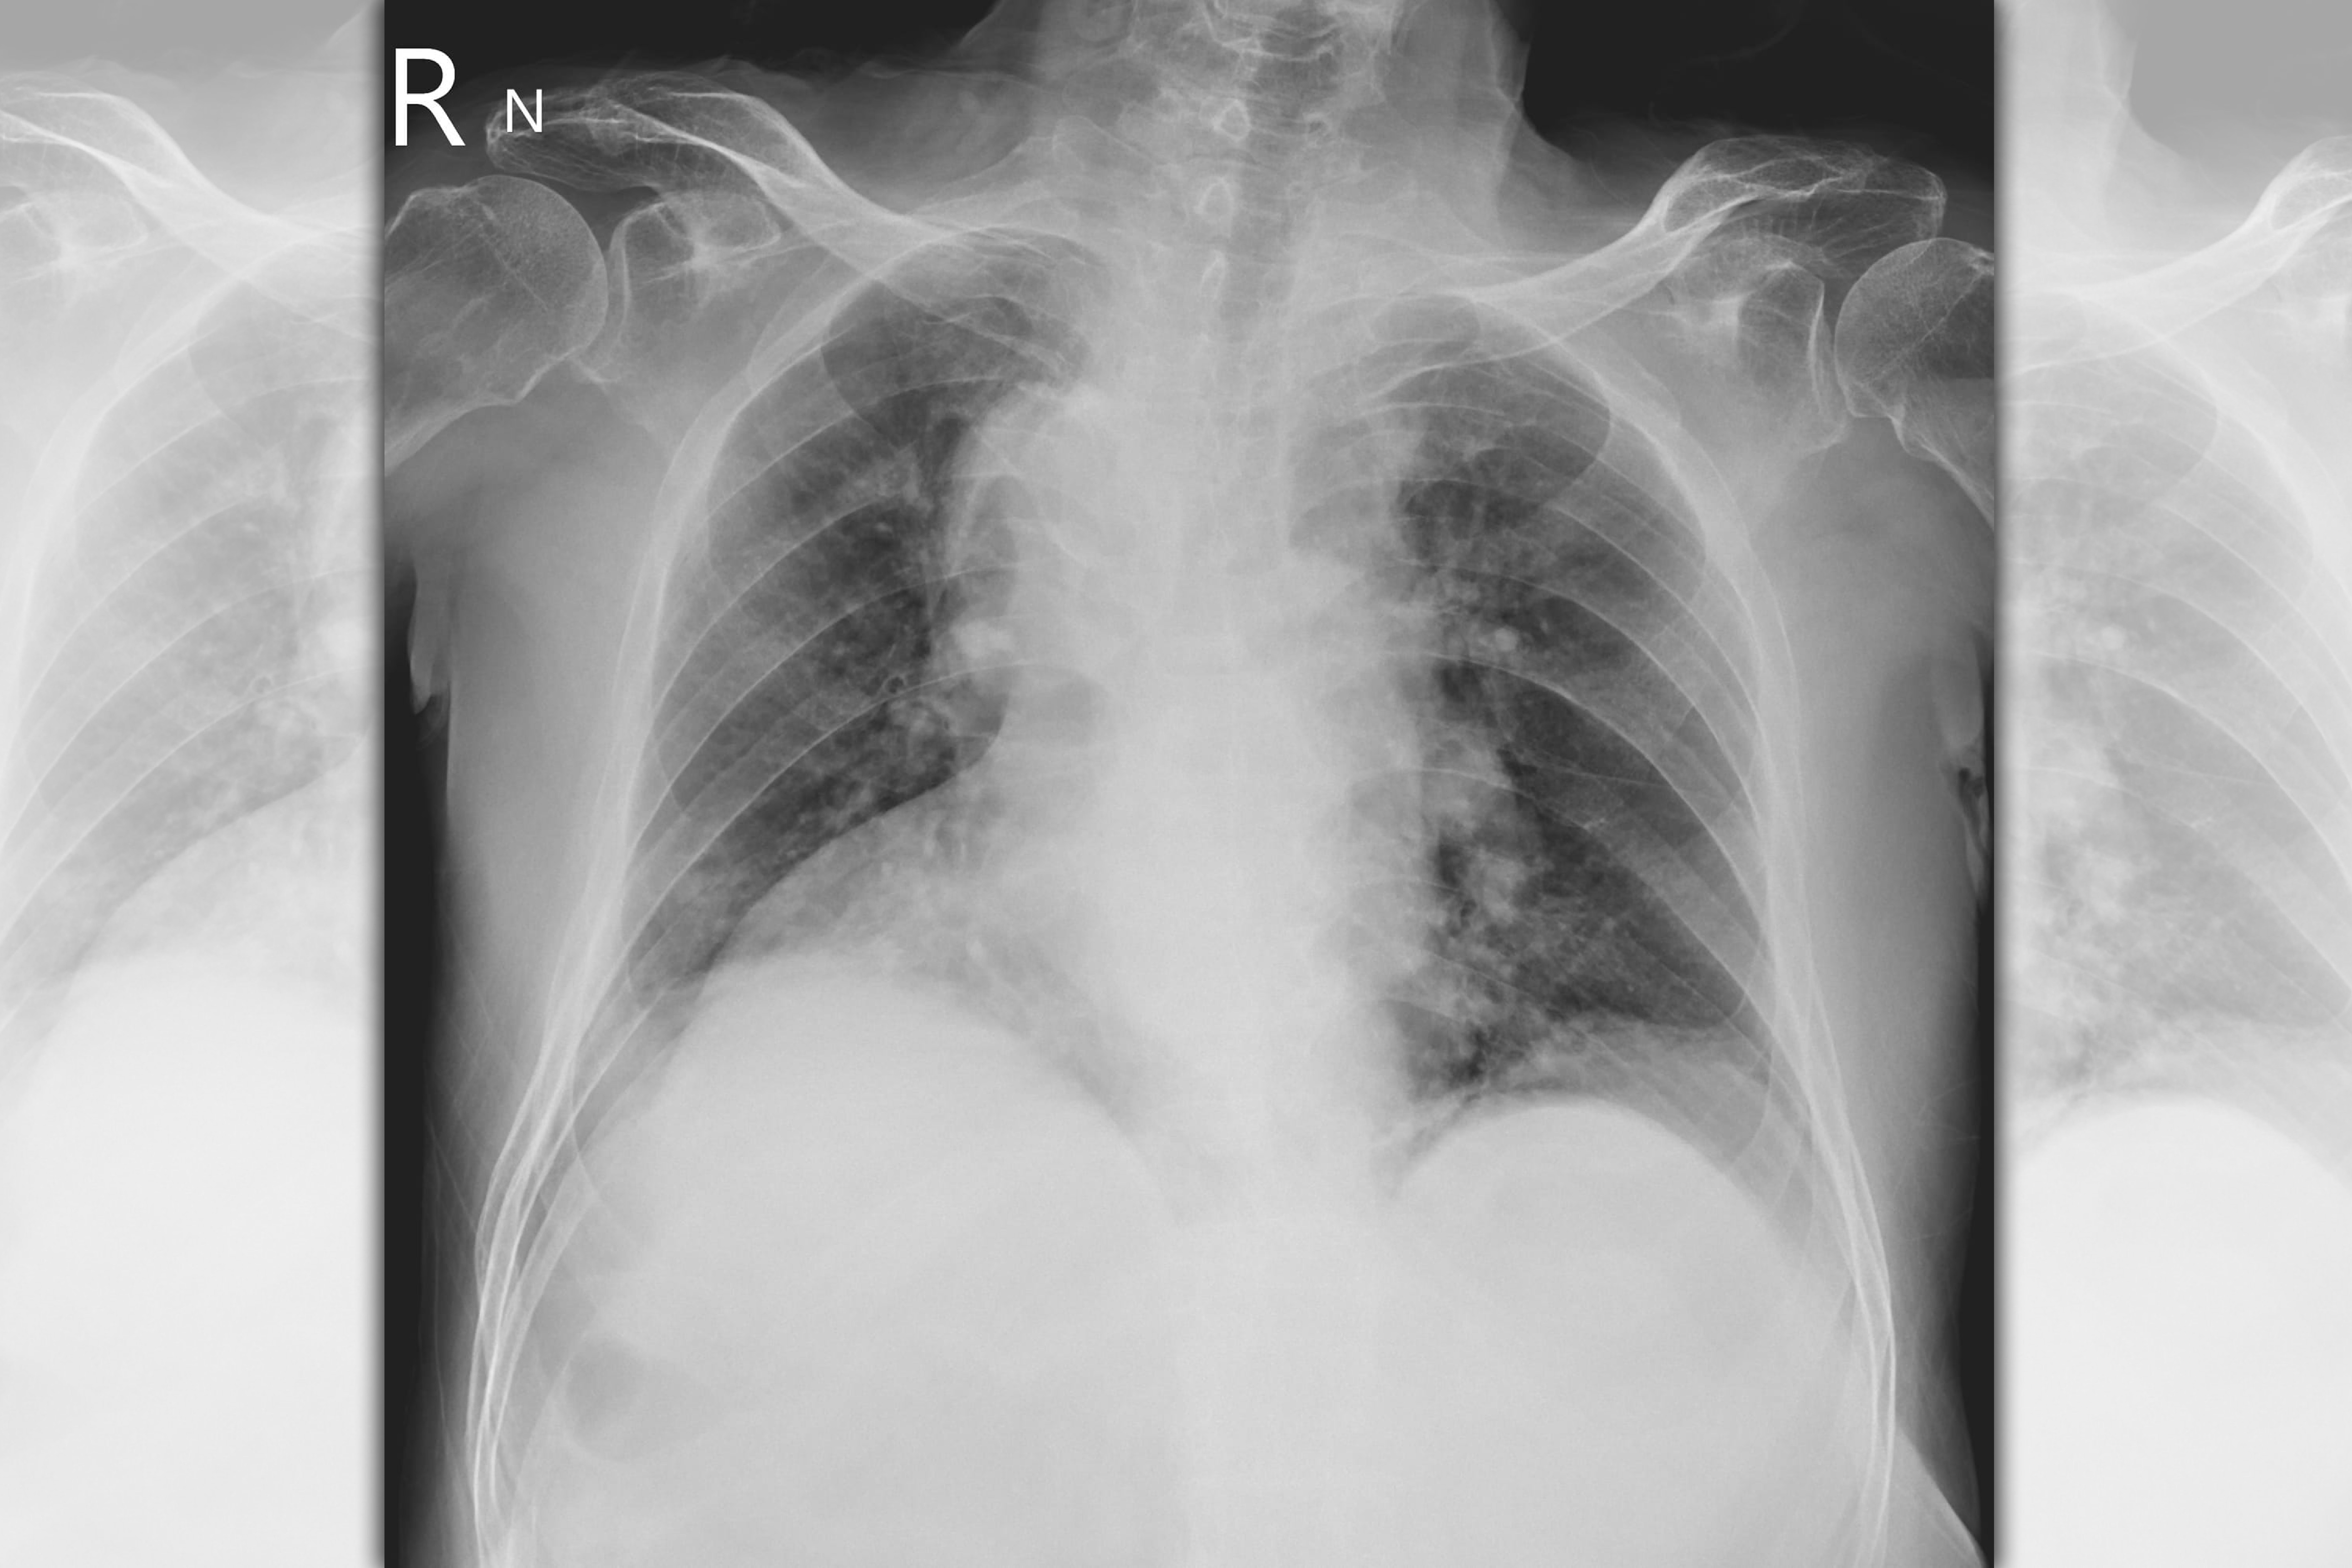

北市聯醫陽明院區胸腔科主治醫師蘇一峰日前在臉書po文分享,遇到一名70歲患者擁有萬中無一的身體構造,他替老翁拍攝胸腔X光後驚呼「哇!伯伯,你的身體很特別喔!」並告知老翁「你的心臟在右邊,而肝臟在左邊,全身的的內臟器官走向左右相反喔!有人跟你說過嗎?」沒想到患者笑說「沒有人跟我說過,今天才知道」。

蘇一峰解釋,「器官轉位(situs inversus):發生機率小於萬分之一,有另外一種類似的型態是只有心臟左右相反(Dextrocardia)右位心(Dextrocardia):發生的比率則比較常見一點,全身器官左右正常,但是只有心臟是左右顛倒!」

蘇一峰補充表示,「器官轉位的病人,有些合併其他疾病,會引起呼吸道的問題,氣管擴張症和鼻竇炎和不孕!台灣現在醫藥發達,器官轉位的問題常常小時候就會被發現,病人在照胸腔X光片中被發現」。